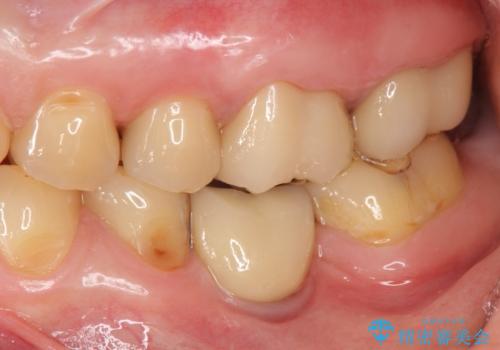

・咬合機能の回復 →セラミッククラウンの製作

深い虫歯・根尖性歯周炎・咬合機能の回復の問題を解決し良好な治療結果を得ることができました。